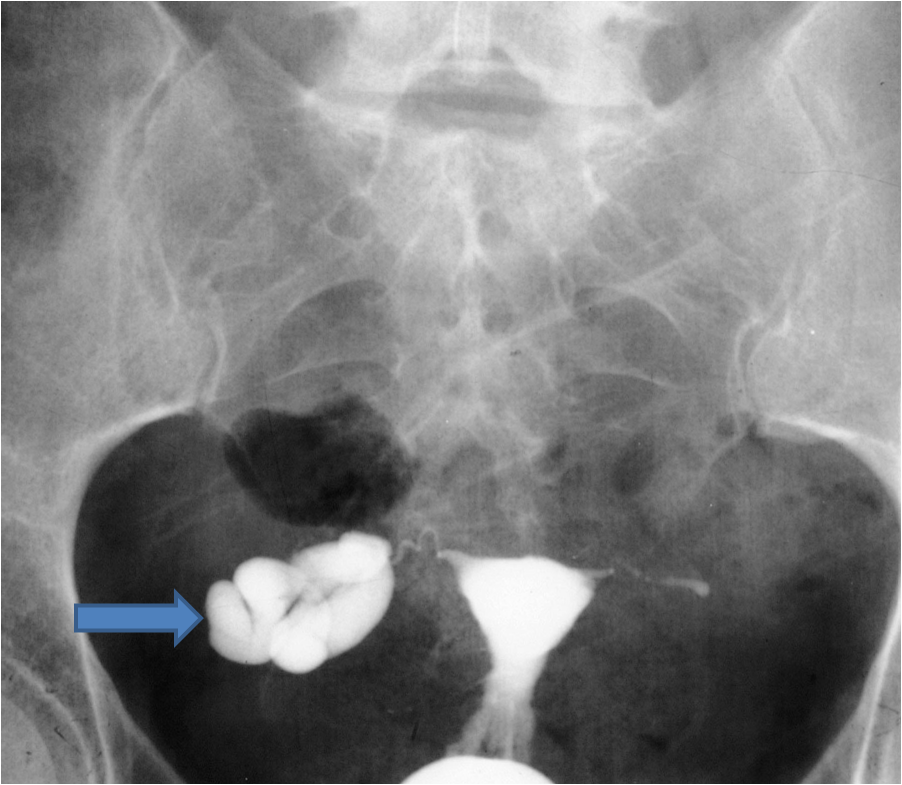

An hsg involves injecting dye into the tubes and getting an X-ray image of your tubes.

An HSG test is used to investigate any issues that may be causing a woman to experience difficulty becoming pregnant by evaluating the shape of the uterus and looking for blockages in the fallopian tubes.

A hydrosalpinx is usually very easy to see on HSG possible but more difficult to see on saline sonogram.